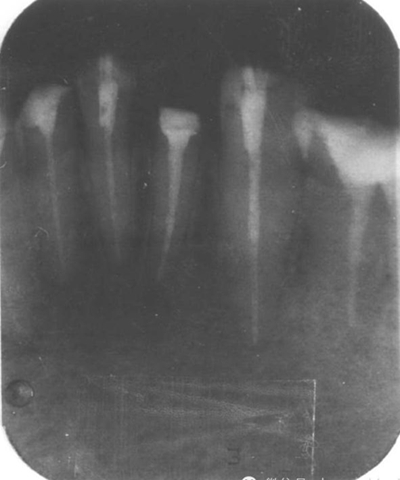

4.用匹配的鉆石擴大至最初的直徑,用X光檢查。

5.重新安裝新的樁核等材料。通過X光片檢查以上步驟。

手術(shù)后